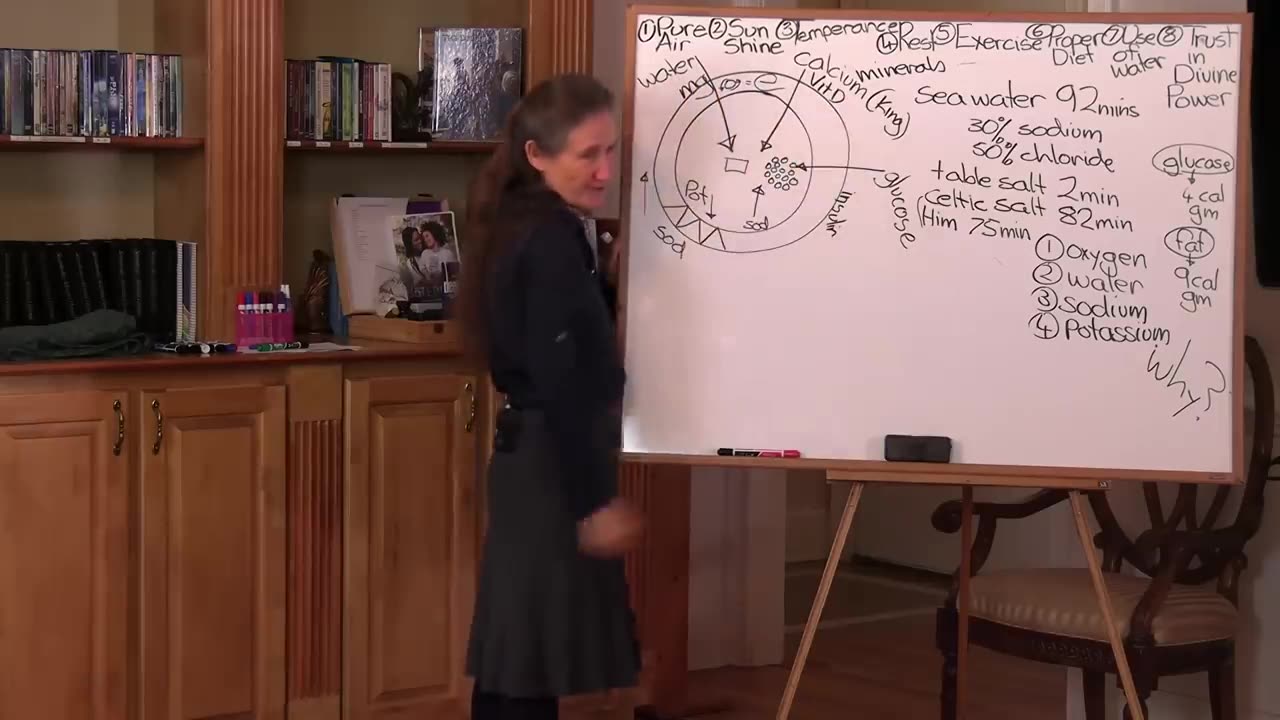

BARBARA O’NEILL WHAT ARE BONES MADE OF?

Barbara ONeill -Recipe for Flu Bomb

Barbara O’Neill-Struggling with constant phlegm or bloc...

Barbara O’Neill-Detoxification and The Liver Part 4 (th...

Barbara O’Neill-Detoxification and The Liver Part 3

December 06, 2025

Barbara O’Neille- Detoxification and The Liver Part 3

Barbara O’Neill-Detoxification and The Liver Part 2

December 03, 2025

Barbara O’Neill-Detoxification and The Liver Part 1

Barbara O’Neill-Why a rebounder is so important for the...

December 02, 2025